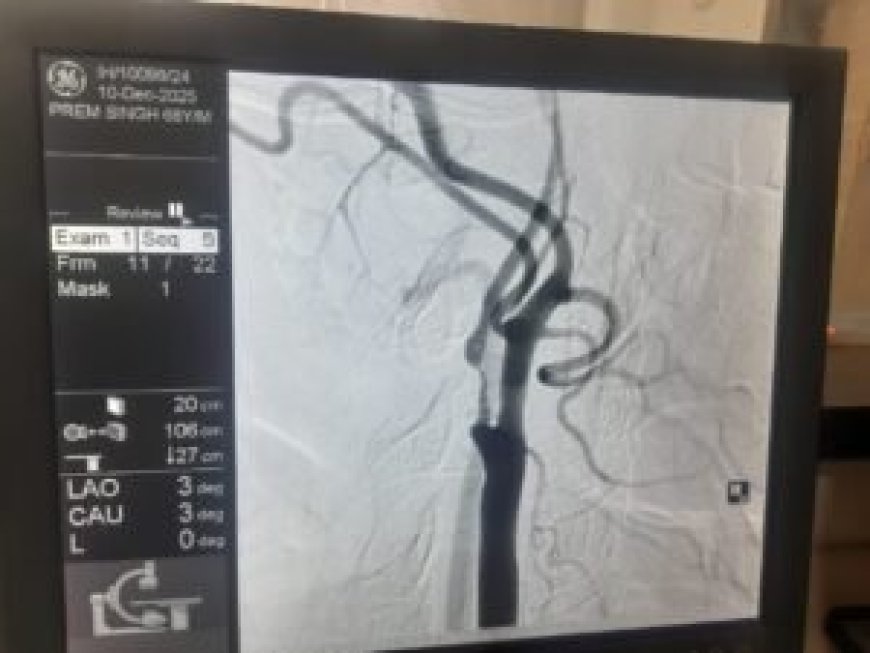

देहरादून : VELMED Hospital में एक महत्वपूर्ण चिकित्सकीय उपलब्धि हासिल हुई है। यहां 69 वर्षीय वरिष्ठ नागरिक प्रेम सिंह में दोबारा स्ट्रोक (लकवा) के जोखिम को रोकने के लिए जटिल Carotid Endarterectomy सर्जरी सफलतापूर्वक पूरी की गई। यह देहरादून में इस स्तर की उन्नत न्यूरो-वैस्कुलर सर्जरी के रूप में एक उल्लेखनीय कदम माना जा रहा है।

एक साल पहले प्रेम सिंह को स्ट्रोक हुआ था, जिससे उनके शरीर के बाएं हिस्से में कमजोरी आ गई थी। हालिया जांच में पता चला कि उनकी दाहिनी कैरोटिड आर्टरी में 95-99% तक गंभीर रुकावट थी, जो भविष्य में फिर से स्ट्रोक का बड़ा कारण बन सकती थी।

डॉक्टरों की मल्टीडिसिप्लिनरी टीम ने स्टेंट लगाने के बजाय सर्जरी को अधिक सुरक्षित विकल्प माना, क्योंकि रक्त नली में मौजूद प्लाक बहुत नरम और नाजुक था, जो टूटकर मस्तिष्क तक पहुंच सकता था। इसलिए Carotid Endarterectomy की सिफारिश की गई, जिसमें गर्दन की धमनी को खोलकर जमा प्लाक को सावधानी से निकाला जाता है।

सर्जरी डॉ. रोहित चौहान (सर्जन, जीबी पंत अस्पताल दिल्ली से प्रशिक्षित) द्वारा की गई। ऑपरेशन के दौरान Pruitt–Inahara Shunt जैसे विशेष उपकरण का उपयोग किया गया, जिससे सर्जरी के दौरान मस्तिष्क में रक्त प्रवाह निरंतर बना रहा और स्ट्रोक का खतरा न्यूनतम रहा। सर्जरी में बड़े, नरम और वसा युक्त प्लाक के टुकड़े निकाले गए, जिससे टीम का निर्णय पूरी तरह सही साबित हुआ।